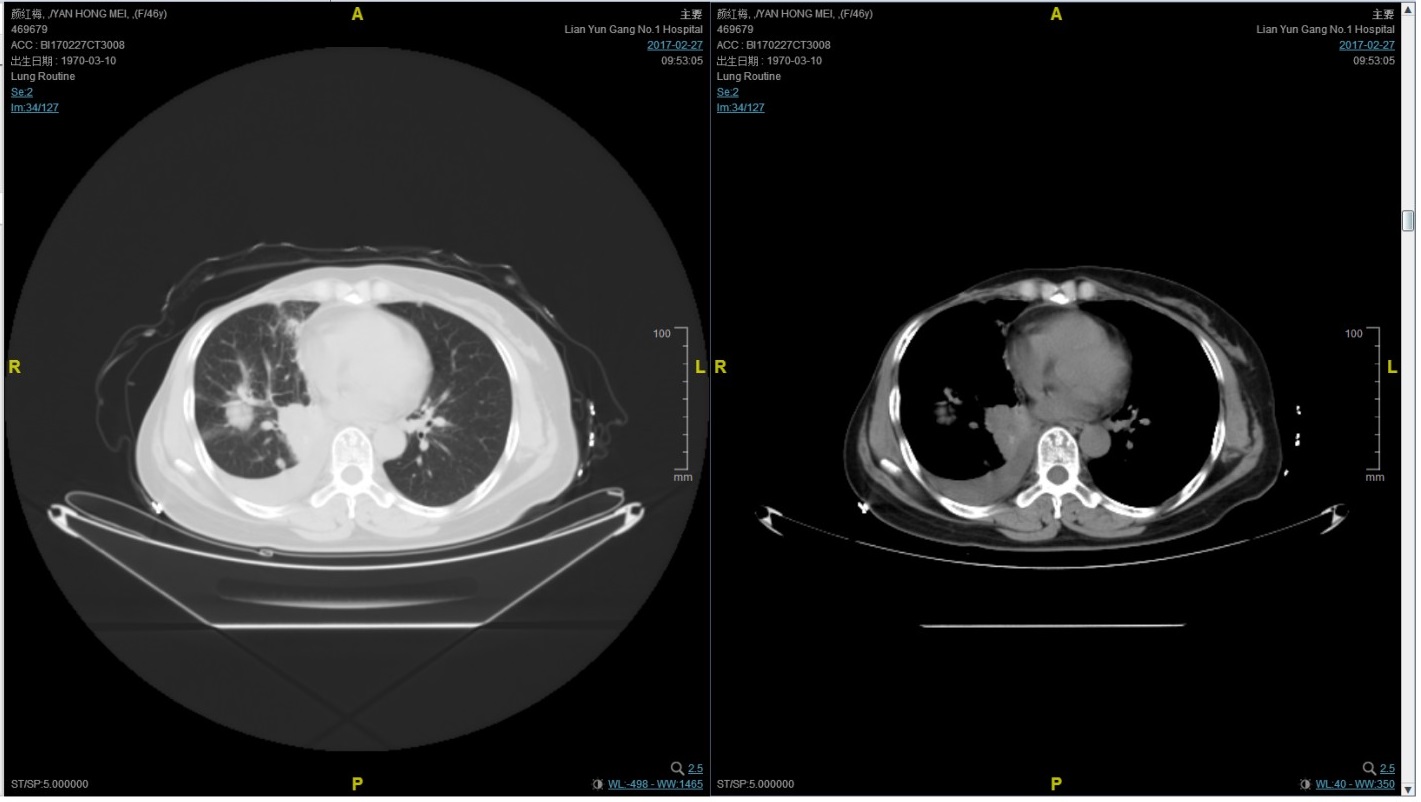

2017-02-27患者因气喘胸闷再次就诊。患者肺部病灶进展,同时出现肝脏转移。再次给予曲妥珠单抗+长春瑞滨化疗一周期,效果不佳,推荐换用TKI治疗,患者放弃治疗。PFS3=12个月。

患者颜X X,女,发病年龄43岁。2010.12.01因体检发现右乳质硬、无痛性肿块住院治疗。入院查体肿块约2.5cm × 1.5cm。考虑诊断为右侧乳腺癌。2010.12.06在我院全麻下“右乳癌改良根治术”。术后病理:(右)乳腺浸润性导管癌,组织学分级Ⅲ级;乳头、皮肤未见癌累及,同侧腋窝淋巴结转移(19/19)。免疫组化:ER(-),PR(-),C- erbB-2(3+)。术后诊断右乳浸润性导管癌并右侧腋窝淋巴结转移(pT2N3M0,IIIC期,HER2阳性型)。术后于2011-01-06起在连云港市第一人民医院给予AC方案化疗4周期,2011-03-20给予右胸壁+右锁骨上下淋巴引流区放疗Dt50Gy/25f,2011-05-26予TH方案化疗4周期(曲妥珠单抗d1首次480mg,以后360mg)共4周期。后续予以曲妥珠单抗360mg(每21天为一周期)维持治疗1年,末次使用曲妥珠单抗的时间在2012年5月,后定期随访,病情稳定。2013-11-23全面复查发现肺转移。 DFS=35个月。2013-11-26起给予曲妥珠单抗(440mg d1)/脂质体紫杉醇(240mg d2)/CBP(500mg d2)方案化疗一个周期,出现Ⅱ度骨髓抑制,因患者主诉乏力明显,后修改方案曲妥珠单抗(330mg 每 3周重复)/脂质体紫杉醇(120mg d1+d8+d15,每4周重复)化疗,化疗过程顺利,患者无明显骨髓抑制,无乏力主诉,于2014-02-11全面复查,疗效评价为PR。继续曲妥珠单抗+脂质体紫杉醇(共六周期)治疗,疗效评价CR。后续予以曲妥珠单抗维持治疗,随访病情稳定。2015年4月,患者肺部病灶复发。给予曲妥珠单抗+希罗达治疗(希罗达1500mg,一天两次口服)。PFS1=17个月。2016-2-18,肺部病灶进展,肺内转移病灶增多。PFS2=10个月。从2016-2-19开始给予紫杉醇+曲妥珠单抗治疗,紫杉醇240mg,3周重复,曲妥珠单抗330mg三周重复。患者末次应用曲妥珠单抗和紫杉醇时间为2016-6-24,紫杉醇共应用4周期。CT评价SD。继续曲妥珠单抗维持治疗,且自服中药。2017-02-27患者因气喘胸闷再次就诊。患者肺部病灶进展,同时出现肝脏转移。再次给予曲妥珠单抗+长春瑞滨化疗一周期,效果不佳,患者放弃治疗。PFS3=12个月。